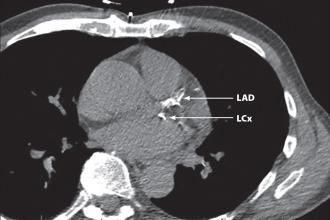

Atherosclerosis, a type of chronic inflammation that is marked by the buildup of lipid-rich plaque within the walls of the arteries, is the leading cause of cardiovascular disease, including coronary... Read More